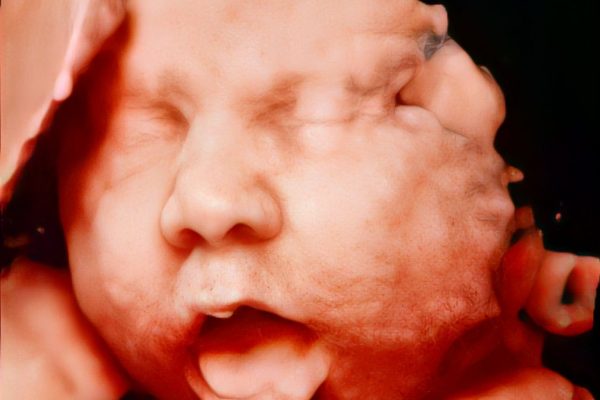

Ultrassonografia Obstétrica:

É um exame de imagem não invasivo e indolor, que utiliza ondas sonoras de alta frequência para visualizar a saúde e o desenvolvimento do feto durante a gestação.

O exame ajuda no estudo e acompanhamento, desde o começo gestacional, para identificação do número de embriões, acompanhamento do desenvolvimento fetal, rastreio de alterações morfológicas, passando por todas as semanas de gestação, para adequada avalição da vitalidade fetal.

A Medicina Fetal é uma especialidade médica que se dedica ao diagnóstico e tratamento de problemas de saúde que afetam o feto durante a gestação. O objetivo é identificar precocemente qualquer problema que possa interferir na saúde do feto e, consequentemente, na sua vida após o nascimento.